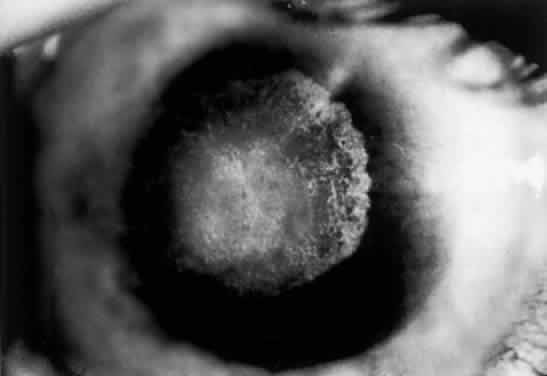

DIAGNOSIS. This syndrome should be suspected clinically. Serum copper levels, as well as ceruloplasmin levels, are low. More precise studies requiring measurement of the turnover of injected radioactive copper may be performed, or copper levels can be determined in liver biopsy specimens. DIFFERENTIAL DIAGNOSES. Pigmented corneal rings clinically identical to Kayser-Fleischer rings have been reported in non-Wilsonian liver diseases, including primary biliary cirrhosis, progressive intrahepatic cholestasis of childhood, and chronic active hepatitis. Although these diseases cause an elevated level of copper in the blood, urine, and liver, only in Wilson's disease are subnormal levels of ceruloplasmin present.56 Pigmented corneal rings have also been associated with multiple myeloma57; and a patient with a poorly differentiated adenocarcinoma of the lung, associated with IgG monoclonal gammopathy and hypercupremia, presented with copper deposition on the cornea and lens.58 PATHOLOGY. Electron microscopic, x-ray energy spectroscopic, and atomic absorption spectroscopic studies of the Kayser-Fleischer rings have revealed electron-dense granules rich in copper and sulfur in both the peripheral and the central region of the cornea, but more abundantly at the periphery. The association of copper with sulfur suggests that a sulfur-containing moiety functions in binding copper.59 MANAGEMENT. D-penicillamine (Cuprimine) is an extremely effective chelating agent because of its ability to mobilize copper from the tissues and increase its excretion in urine.52,60 Treatment of Wilson's disease with penicillamine is effective when started before there is active liver disease. After prolonged treatment with penicillamine, Kayser-Fleischer rings may fade, neurologic signs may clear, and liver function abnormalities may disappear. However, Kayser-Fleischer ring regression does not correlate with neuropsychiatric improvement.61 With D-penicillamine or after liver transplantation,62 Kayser-Fleischer rings disappear in reverse order to their formation. In most patients, the neurologic and hepatic lesions remit; hence the importance of recognizing the significant corneal pigment rings. Lowe's Oculocerebrorenal Syndrome This is an X-linked recessive metabolic disorder of unknown etiology. First recognized as a clinical entity by Lowe and co-workers,63 it occurs only in males and is characterized by mental and growth retardation, hypotonia, aminoaciduria, reduced ammonia production by the kidneys, rickets, and eye signs. The syndrome is listed here because aminoaciduria is one of the symptoms. OCULAR FINDINGS. The most prominent ocular findings are congenital cataracts (over 96%) and congenital glaucoma (over 50%). A miotic pupil is common, but the retina is usually normal. A mild corneal haze has been reported, but this is probably the result of glaucomatous ocular hypertension. DIAGNOSIS. This disorder should be considered in any male infant with both congenital cataracts and congenital glaucoma. In carrier females, the lenticular opacities are punctate, white to gray in hue, and vary in size from microns to several millimeters. Unlike congenital nuclear opacities, lenticular opacities are present in all layers of the cortex, indicating that they are well formed in adult life. Subcapsular, plaque-like cataracts are seen predominantly in older obligate carriers. Because female carriers have an identifiably higher number of lens opacities than do age-matched controls, genetic counseling may be indicated because 50% of their female offspring are expected to be carriers.64 Biochemical findings are typical and include metabolic acidosis and renal tubular acidosis. The basic enzyme deficiency is unknown, but may be related to biochemical abnormalities in glycosaminoglycan metabolism. The urinary findings include proteinuria, generalized aminoaciduria, organic aciduria, and on occasion, glycosuria.65 DIFFERENTIAL DIAGNOSIS. Rubella can cause both congenital cataracts and glaucoma but usually produces only one or the other. MANAGEMENT. A lensectomy-vitrectomy is indicated for visual rehabilitation in patients with dense cataracts. Although all Lowe's syndrome patients are retarded, the degree of retardation is not necessarily severe. When these patients are visually rehabilitated by surgery and subsequent refractive correction, they function better than do those patients with visual stimuli deprivation.66 Porphyria CONGENITAL ERYTHROPOIETIC PORPHYRIA. This disease, also known as Gunther's disease, is an autosomal-recessive disorder. It is caused by a deficiency of uroporphyrinogen III synthase activity, resulting in an overproduction of porphyrins (type I) for which the body has no use. Different molecular defects have been detected.67 The clinical signs include hydroa aestivate (a vesicular or bullous eruption of the face, backs of the hands, and other exposed areas of the body), erythrodontia (brownish discoloration of the teeth), hypertrichosis, and splenomegaly.68 Neurologic symptoms, hypertension, and abdominal colic are not found. Ocular Findings. Ocular manifestations of this disorder include cicatricial ectropion, loss of eyelashes and eyebrows, bilateral exophthalmos, optic atrophy, retinal hemorrhages, and chorioretinitis.69–71 Conjunctivitis may result in marked scarring and adhesion of the conjunctiva to the sclera. Decreased corneal sensitivity, corneal scarring and vascularization, corneal perforation at the limbus, and scleromalacia may occur. Histopathology of tissue from a patient who underwent a penetrating keratoplasty and conjunctival resection revealed a thickened basement membrane of the vessels within the conjunctival and corneal stroma. Microfibrillar material was seen in the extracellular spaces of the conjunctival stroma. Inflammatory cells were noted in the corneal stroma, and there was a loss of keratocytes. Descemet's membrane lacked the normal fetal and postnatal banding and the endothelium was severely damaged.72 The changes in the vessels and conjunctival stroma were similar to those described in the skin of porphyria patients exposed to ultraviolet light. Laboratory Investigations. Normochromic anemia and excessive excretion of uroporphyrin I and coproporphyrin I in urine and feces are found. The diagnosis should be confirmed by detection of decreased uroporphyrinogen III synthase activity. VARIEGATE PORPHYRIA. This hepatic porphyria is characterized by acute attacks involving abdominal and neurologic manifestations, as well as by chronic skin lesions that are caused by photosensitivity. Ocular Findings. In addition to the previously mentioned ocular signs, optic neuritis, optic atrophy, and exudates similar to those in acute intermittent porphyria are seen in affected homozygotes.70 Laboratory Investigations. Analysis of urine and stools reveals increased levels of protoporphyrin, coproporphyrin, uroporphyrin, aminolevulinic acid, and porphobilinogen, the latter being present only in acute attacks.68,70,71 Management. Intravenous heme leads to a rapid recovery of acute attacks. No specific therapy for ocular lesions is available. Scleral patch grafts have been used successfully to treat the scleromalacia perforans that develops in some of these patients.73 Amyloidosis Amyloid deposition produces dysfunction in any organ by replacing its functioning mesenchymal or parenchymal cells. All amyloid proteins are insoluble fibrinous proteins that share a unique fibrillar ultrastructure. Depending on the origin of the amyloid protein, the amyloid fibrils deposit either in certain organs or systemically. Amyloid deposition does not incite any inflammatory response; however, a foreign body giant cell reaction may be seen occasionally around deposits in the ocular adnexa.74 Amyloidosis can be classified as primary (localized and systemic), secondary (localized and systemic), and heredofamilial according to the presence or absence of underlying disease (primary or secondary amyloidosis) and genetic associations (heredofamilial). More recently, amyloidosis has been classified according to the protein precursor. The nomenclature for this classification includes A (for amyloidosis) followed by the initial of the protein precursor (e.g., AL for amyloidosis with light chain immunoglobulins as precursors).75 The most common type of systemic amyloidosis currently seen is the light chain amyloidosis (AL), which is associated with primary amyloidosis and sometimes with multiple myeloma. Fifteen to 20% percent of patients with myeloma have amyloidosis; fewer than 20% of patients with amyloidosis have myeloma.76 In secondary systemic amyloidosis the major amyloid deposit is protein AA, a degradation product of a serum acute phase reactant, serum amyloid A (apoSAA). Histologic examination of amyloid deposition has shown a pericollagenous distribution associated with the primary and myeloma-related types (pattern type I) and perireticulin deposition in the secondary form of amyloidosis, associated with parenchymatous organ invasion (pattern type II). PRIMARY AMYLOIDOSIS (SYSTEMIC AND NONSYSTEMIC TYPES). Primary amyloidosis is the form associated with clinically important depositions of amyloid in the eyes or ocular adnexa.74,77 Ocular Findings CORNEA Nonsystemic Familial Type. Lattice corneal dystrophy (Biber-Haab-Dimmer) is usually considered to be a localized amyloidosis of the cornea and could be classified as a special type of primary localized autosomal dominant amyloidosis (see corneal dystrophies section) (Fig. 6).78 Rarely, a form of primary familial amyloidosis of the cornea may occur. The lesions appear as centrally located, raised, gelatinous masses with a mulberry-like surface (Fig. 7).79

Nonfamilial Type. Accumulations of amyloid in the cornea without apparent systemic involvement or a hereditary pattern have been described. Most often this occurs as the result of pre-existing ocular disease.80 Systemic Familial Type. Rarely, patients with lattice corneal dystrophy may have a familial primary systemic amyloidosis known as Meretoja syndrome. These patients develop lattice dystrophy in young adulthood and, in later years, skin changes, cranial nerve palsies, peripheral neuropathies, and visceral complaints. The lattice dystrophy that develops with systemic involvement is milder with regard to visual loss but more extensive in that it reaches to the corneal periphery without the peripheral lucid interval seen with localized lattice.81 CONJUNCTIVA. Clinically detectable conjunctival involvement is not a feature of systemic amyloidosis. However, nonfamilial amyloidosis confined to the conjunctiva has been reported as an example of primary amyloidosis. Conjunctival amyloidosis is often asymptomatic and may be present for years before the patient seeks medical attention. Typically, there is a discrete, nonulcerative, yellow, waxy, firm, nontender subconjunctival swelling (Fig. 8). This may be located in the palpebral fornix or bulbar conjunctiva, including the limbal area. The conjunctival area is usually smooth but may be friable and may show recurrent bleeding. However, antecedent local diseases have been incriminated in this amyloid deposition.77 EYELID. The skin of the eyelid is the site of predilection for the characteristic cutaneous eruption of primary systemic amyloidosis.77 Typically, the lesions are symmetric, bilateral, small, smooth, and discrete or confluent papules. These lesions may be yellow and waxy or purple and hemorrhagic. A positive family history is often present. Primary localized amyloidosis does not affect the skin of the eyelids.7 VITREOUS. Vitreous opacities in amyloidosis may be uniocular or they may be asymmetric if both eyes are involved; these opacities may be the presenting feature of systemic amyloidosis. Vitreous involvement is much more common in primary familial systemic amyloidosis (more than 20 cases reported) than in nonfamilial amyloidosis (only 5 cases reported).82 ORBIT. Orbital involvement does occur in primary nonsystemic amyloidosis; proptosis is a prominent feature. Orbital amyloidosis can present as an acquired isolated sixth nerve palsy in a young adult.83 Amyloid also occurs in the orbits of some patients with primary familial systemic amyloidosis. NEURO-OPHTHALMIC MANIFESTATIONS. Pupillary abnormalities are the most common neuro-ophthalmic sign found in primary familial systemic amyloidosis. Pupils have been described as dilated and unequal with absent or sluggish reactions to light, which at times may be accompanied by poor accommodative responses.74 Amyloid may be deposited in ciliary nerves. External ophthalmoplegia, diplopia, and optic neuropathy have been reported in some cases of familial amyloidosis. SECONDARY SYSTEMIC AMYLOIDOSIS. Secondary systemic amyloidosis is associated with a number of underlying afflictions that have a significant chronic inflammatory component, such as tuberculosis, osteomyelitis, and leprosy. Small, clinically insignificant deposits of amyloid in the eye have been described rarely, and ophthalmologic signs attributable to the presence of amyloid are virtually unknown.77 SECONDARY LOCALIZED AMYLOIDOSIS. This form of amyloidosis has been reported to occur in association with trichiasis,84 granular corneal dystrophy,85 and keratoconus,86 or after chronic keratitis. Diagnosis. Amyloidosis must be suspected on clinical grounds. Definitive diagnosis depends on histochemical reactions, including metachromasia with crystal violet, fluorescence with thioflavin T, birefringence and dichroism with Congo red, and positive staining with direct cotton dyes such as Sirius red. The mere recognition of amyloid in an ocular structure can no longer be considered a complete diagnosis. In primary systemic amyloidosis, the diagnosis is readily made by pathologic examination of the vitreous aspirate. The possibility of amyloidosis in extraocular sites, underlying or associated ocular disorders, familial aspects, and myelomatosis and other immunoglobulin abnormalities must be considered. Management. Medical treatment may be specific for the various amyloidoses. Liver transplantation has been successful in some familial cases. Treatment of the underlying inflammatory condition is of questionable benefit in secondary amyloidosis; however, in primary amyloidosis, where a presumed monoclonal plasma cell secretes excess light chain, alkylating agents have been used with modest impact on survival. Recently, the combination of melphalan and prednisone in this setting was shown to be superior to colchicine, leading to prolonged survival.87 When surgery is indicated, the treatment of choice for vitreous involvement of amyloidosis is vitrectomy. Pars plana vitrectomy can be effective in restoring visual acuity, although recurrences are common. Reopacification of the retrolental vitreous is the most common reason for vitrectomy revision, which is required in 24% of patients.88 Penetrating keratoplasty may be required for advanced corneal disease although the deposition frequently recurs in the graft. Phototherapeutic keratectomy with excimer laser has been used for superficial depositions in the cornea.89,90 Gout and Urate Keratopathy Gout is a clinical disorder of purine metabolism manifested by hyperuricemia, recurrent attacks of acute arthritis that are usually responsive to colchicine, and on occasion, tophaceous deposition of monosodium urate. Nephropathy is a frequent complication.91 Primary gout is usually attributed to an inborn error of metabolism. A deficiency of hypoxanthine-guanine phosphoribosyl transferase has been found in familial gout and may represent the enzymatic deficiency in at least one variety of the disease.92 The largest subgroup consists of patients in whom the biochemical defect is as yet undefined. Other enzymes may be involved. Secondary gout or hyperuricemia may occur in toxemia of pregnancy and chronic renal insufficiency, as well as in other conditions that may be associated with breakdown of cell nuclei, such as malignant lymphomas, chronic myelogenous leukemia, hemolytic anemia, and primary polycythemia. Increased endogenous urate production, as well as impaired renal urate excretion, has been cited as the basis for the hyperuricemia. The characteristic pathologic feature of gout is the deposition of urate crystals in articular and periarticular structures. In the eye, precipitation of urate crystals has been described in the lens, sclera, tarsal plates, tendons of extraocular muscles, and cornea.93 The ocular deposition of urate crystals supports the clinical finding that urate deposits develop in avascular rather than vascular tissue. Genetic factors may include both cumulative gene action and single-gene effects. OCULAR FINDINGS. Clinical manifestations of ocular gout include chronic hyperemic conjunctivitis, scleritis, episcleritis (Fig. 9), and tenonitis. In the past, uveitis has been associated with gout; but in a review of 69 patients with severe gout, none had any evidence of uveitis, either past or present.94 Monosodium urate crystals may be deposited in the corneal epithelium.95 The urate crystal deposition may offer one of two possible appearances. Slit lamp examination shows a fine, golden-yellow, scintillating crystal formation, diffusely distributed in the cornea, more heavily in the interpalpebral fissure and extending to the limbus. These crystals appear epithelial and subepithelial; they are best visualized by retroillumination. Crystals interpreted as urates also have been described in band keratopathy occurring in a patient with gout.96 This keratopathy cannot be differentiated from calcium deposits solely by slit lamp examination. The site of urate crystals in the corneal epithelium is intranuclear.95 Urate-like crystals also have been seen in the corneal stroma in a disease termed keratitis urica. This is probably a localized dystrophic corneal disease and not associated with gout.96 DIAGNOSIS. A high index of suspicion is necessary to establish gout as a contributing factor to corneal crystals, band keratopathy, conjunctivitis, and iritis. Accordingly, the ophthalmologist should consider gout in the differential diagnosis of every patient with bilateral chronic conjunctivitis. High levels of uric acid in the urine and blood are helpful in establishing the diagnosis. Diuretic therapy is currently one of the major causes of secondary hyperuremia.97 Other causes of corneal crystals include cystinosis and monoclonal gammopathy. (See Table 1 for the differential diagnoses of crystals and band keratopathy.) MANAGEMENT. Allopurinol is the most common antihyperuricemic agent used to treat gout. Long-term use of allopurinol has been associated with lens changes, primarily in the anterior and posterior subcapsular area. Recent evidence, however, suggests that long-term allopurinol therapy has a cataractogenic action only in patients in whom the drug has become photobound within the lens, possibly as a result of exposure to ultraviolet radiation.98 Paraproteinemias: Multiple Myeloma Multiple myeloma is characterized by multiple plasma cell tumors, commonly manifesting themselves as osteolytic bone lesions. The neoplastic cells secrete monoclonal immunoglobulins, which may deposit as amyloid protein in different tissues, and may be excreted in the urine as immunoglobulin light chains (Bence Jones proteinuria). The disease results in bone pain, depletion of blood elements, hypercalcemia, renal insufficiency, amyloidosis, and immune disturbances. The incidence of multiple myeloma increases with age and is around 3 per 100,000. This incidence is equal in men and women, but blacks are affected more commonly than whites.99 Recently, a Herpes virus (HHV-8) has been implicated in the development of the disease.100 OCULAR FINDINGS. The ocular manifestations of multiple myeloma may be divided into two groups: those attributable to plasmacytoma growth in and about the eye, and those attributable to hematologic and serum protein abnormalities.101 The ocular manifestations include intraorbital or intraocular plasmacytomas,102,103 ciliary body cysts,104,105 retinal vascular tortuosity, hemorrhages and exudates,106 and the ophthalmic manifestations of intracranial plasmacytomas (papilledema).106 Crystals may be seen in the lens, and the cornea may show a band keratopathy resulting from the hypercalcemia. Clusters of myeloma cells may occur on the corneal endothelium. Conjunctival involvement in patients with multiple myeloma includes sludging of red cells in conjunctival vessels; occasionally malignant plasmacytomas of the conjunctiva arise anew or in association with advanced multiple myeloma.107 The presence of numerous delicate, scintillating crystals in the cornea has been recognized as a rare manifestation of hypergammaglobulinemia.41,108–110 In some cases, the corneal crystals are interspersed throughout the corneal stroma; in others they are most evident in the anterior cornea,103 including the epithelium.110 Posterior stromal corneal deposits are uncommon. The deposits usually are not vascularized, and corneal sensation is normal. Crystals may be detectable clinically in the bulbar conjunctiva.41,108,109 Aronson and Shaw described corneal crystals as probably consisting of cholesterol41; however, these crystals probably consist of partial or complete immunoglobulins110 (Fig. 10). Cysts of the ciliary body have been reported in 33% to 50% of myeloma patients, and retinal vascular lesions have been reported in up to 66% of these patients.111 Although corneal and orbital involvement are less common, orbital involvement is the first manifestation of systemic disease in about 75% of cases. Primary plasmacytomas may arise in the soft tissues or in the surrounding bones with secondary orbital invasion. The orbital roof and frontal bones often are affected, with resultant proptosis and downward displacement of the globe. The most common clinical signs are eye pain, diplopia, and visual impairment associated with a history of slowly progressive proptosis for weeks to months. Choroidal folds, venous engorgement of the disc, ptosis, and pupillary involvement may occur. Polychromatic, dustlike deposition of copper in Descemet's membrane of the central cornea (with peripheral sparing) and in the anterior and posterior lens capsule occurs when the myeloma protein has strong copper-bonding properties.57 Corneal crystalline deposits also may occur in benign monoclonal gammopathy.110 Corneal opacities also have been reported in a patient with cryoglobulinemia and reticulohistiocytosis.112 DIAGNOSIS. Serum protein electrophoresis, examination of the urine for the presence of Bence Jones protein, and bone marrow aspiration are required. The differential diagnoses must include other causes of corneal crystals (see Table 1). MANAGEMENT. Lamellar keratoplasty has been performed for visual rehabilitation.110 However, the treatment is basically directed toward the systemic disease. Chemotherapy and radiotherapy are effective in reducing the tumor mass in the orbit. Clinical improvement occurs in more than half of patients treated with alkylating agents such as melphalan. Radiotherapy is effective in treating orbital plasmacytomas and localized lytic bone lesions. Hypercalcemia is treated with hydration and intravenous furosemide (to promote urinary calcium excretion), as well as with steroids. The new bisphosphonate agents, such as pamidronate, are effective in correcting the hypercalcemia of multiple myeloma, and have recently been approved by the FDA for prevention of bone fractures in this disease.113 Ciliary body epithelial cysts are usually not diagnosed in life and do not require treatment. Retinopathy may improve with systemic treatment. Both penetrating and lamellar keratoplasties have been performed for advanced corneal disease, but recurrence after lamellar keratoplasty has been reported.110 Marked clearing of the corneal crystals with corresponding improvement of visual acuity has been reported to occur after chemotherapy.114 DISORDERS OF LIPOPROTEIN AND LIPID METABOLISM The plasma lipoproteins are complex water-soluble macromolecules involved in the transport of lipid to and from tissues. These macromolecules contain triglyceride, cholesterol ester, and phospholipid in combination with specific apoproteins. The lipoproteins can be separated by electrophoresis into four main groups; in order of increasing mobility on paper electrophoresis, these are the chylomicrons, β-lipoproteins, prebetalipoproteins, and α-lipoproteins (Table 2). A further characterization based on lipoprotein size and density is achieved by ultracentrifugal analysis. The normal range of plasma lipid concentrations is noted in Table 3.